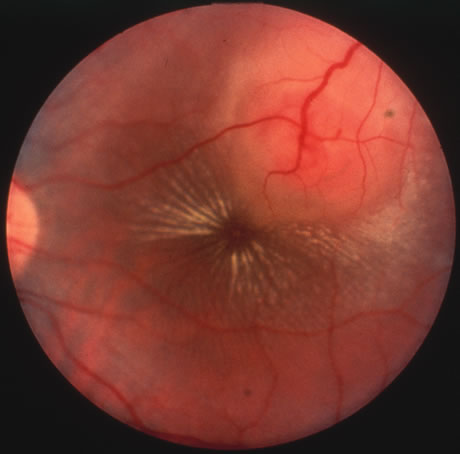

CMV retinitis is common in patients with AIDS. Perivascular granular white or yellowish infiltrates with hemorrhage are typical (Fig. 7). Minimal vitritis or anterior uveitis may be present. The posterior pole, including optic nerve, or peripheral retina may be involved. Optic neuritis may be retrobulbar. Resolution of retinal lesions reveals local retinal atrophy and pigment dispersion. Iridocyclitis may occur secondary to infection of ciliary processes. CMV retinitis in patients with AIDS is considered a poor prognostic sign in terms of life expectancy. Congenital CMV infection may also cause retinitis, as well as anterior uveitis, cataract, and optic atrophy. New foci of retinochoroiditis can develop in later years of congenital infection, and such infants require periodic reexamination as long as virus is shed in the urine.